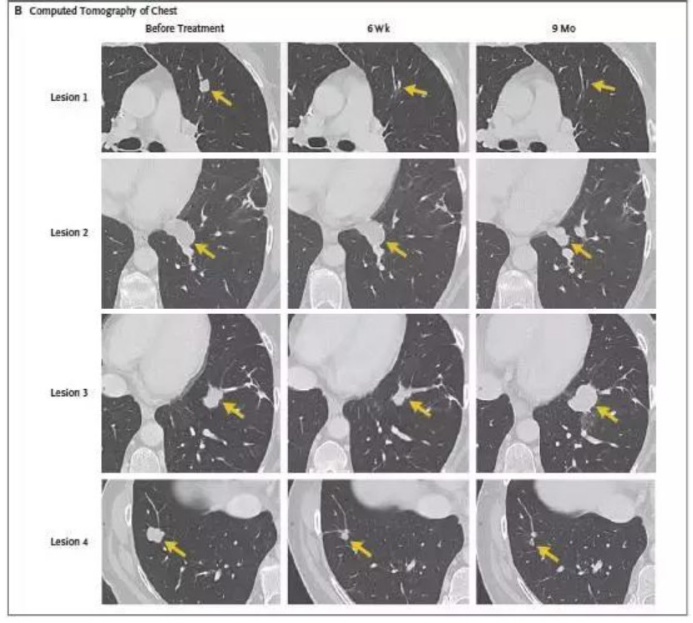

3.转移性结直肠癌患者肿瘤患者经过TIL细胞疗法治疗后,7个肺部的转移灶在几周后都变小乃至消失!